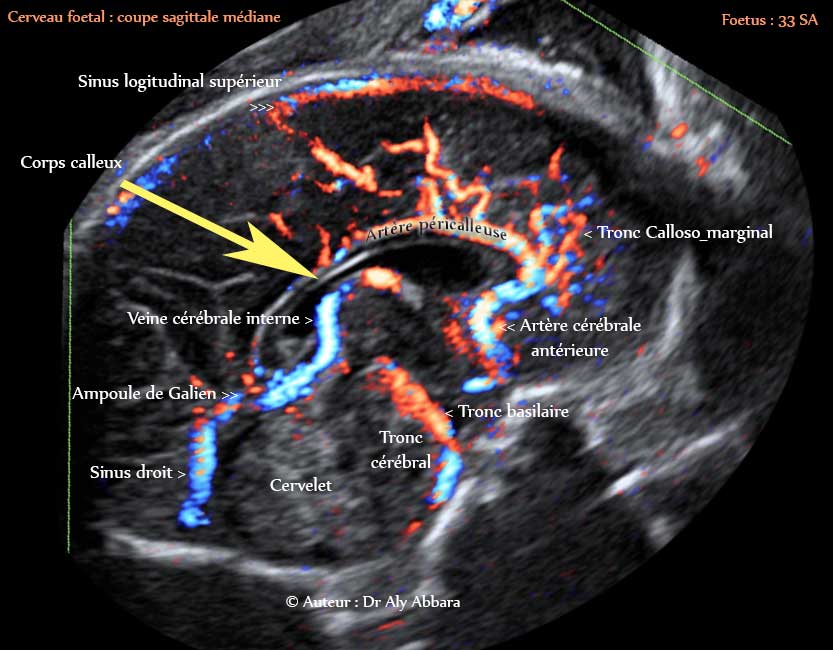

Cerveau : coupe sagittale médiane passant par le corps calleux

Images échographiques montrant le réseau vasculaire artério-veineux principal du cerveau fœtal

Fœtus âgé de 33 SA

Auteur : Dr Aly Abbara